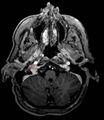

التشخيص

الصور الأضافية